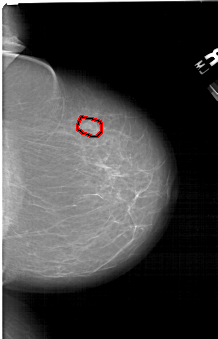

FILE: A_1494_1.RIGHT_MLO.OVERLAY TOTAL_ABNORMALITIES 1 ABNORMALITY 1 LESION_TYPE MASS SHAPE OVAL MARGINS OBSCURED ASSESSMENT 4 SUBTLETY 3 PATHOLOGY BENIGN TOTAL_OUTLINES 1 BOUNDARY |

FILE: A_1494_1.RIGHT_CC.OVERLAY TOTAL_ABNORMALITIES 1 ABNORMALITY 1 LESION_TYPE MASS SHAPE OVAL MARGINS OBSCURED ASSESSMENT 4 SUBTLETY 3 PATHOLOGY BENIGN TOTAL_OUTLINES 1 BOUNDARY |